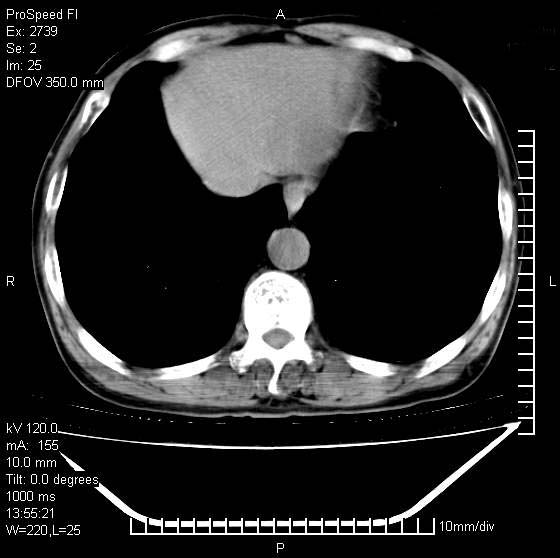

以下是引用andymaomao在2007-12-7 15:54:00的发言:[br]1.双上肺陈旧肺tb灶;[br]2.双中上肺矽肺;[br]3.双肺气肿;[br]4.图中箭头所指乃下腔静脉。

以下是引用山之魂海之韵在2007-12-7 18:59:00的发言:[br]支持矽肺,左肺上叶陈旧性结核,肺气肿。箭头所指乃下腔静脉。下腔静脉显影比主动脉显影迟,增强动脉后迟可以是不均匀的。

以下是引用chengjiaqiu1在2007-12-7 17:49:00的发言:[br]矽肺,左肺上叶陈旧性结核,肺气肿。中箭头所指乃下腔静脉。